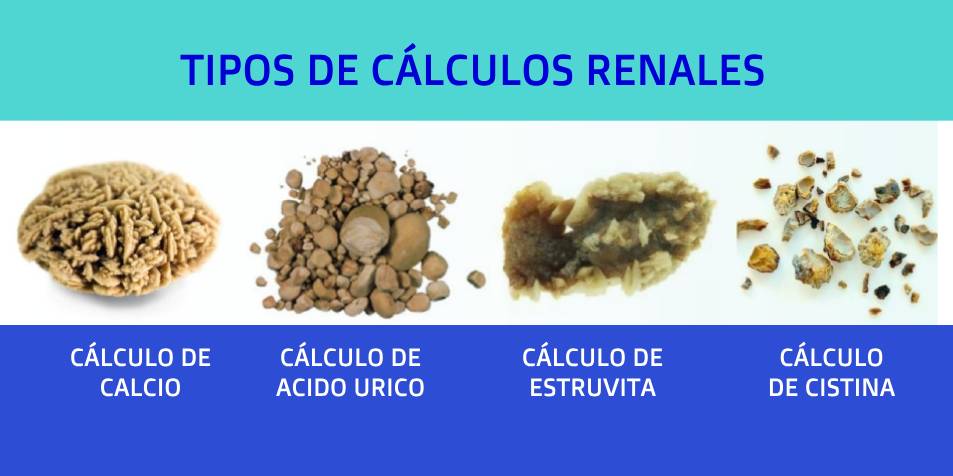

Existen diversos tipos de cálculos, de ahí es que las causas variarán de acuerdo al tipo de litiasis renal con la que nos encontremos.

- La sustancia más común en la formación de estos cristales es el calcio, el cual al combinarse con otras sustancias forman un cálculo. La presencia de este tipo de calculo es frecuente en hombres que bordean los 20 y 30 años de edad.

- La unión de calcio con el oxalato da paso a la constitución de posibles cálculos, el oxalato lo encontraremos en alimentos como las espinacas así mismo en los suplementos de vitamina C.

- Las personas con cistinuria (enfermedad congénita hereditaria) también padecerán de litiasis renal, la creación de los cálculos serán por la sustancia llamada cistina (aminoácido). Afecta tanto la población masculina como femenina.

- El ácido úrico es otra sustancia usual en el origen de los cálculos renales manifestándose en mayor medida en los hombres. En la colectividad de casos se pueden presentar con la gota o después de recibir tratamiento de quimioterapia en algunos tipos de cánceres.

- Para hombre o mujeres que presentan con alta frecuencia infecciones del tracto urinario detectaremos cálculos de estruvita, los cuales suelen crecer mucho y obstruir el riñón, los uréteres o la vejiga.